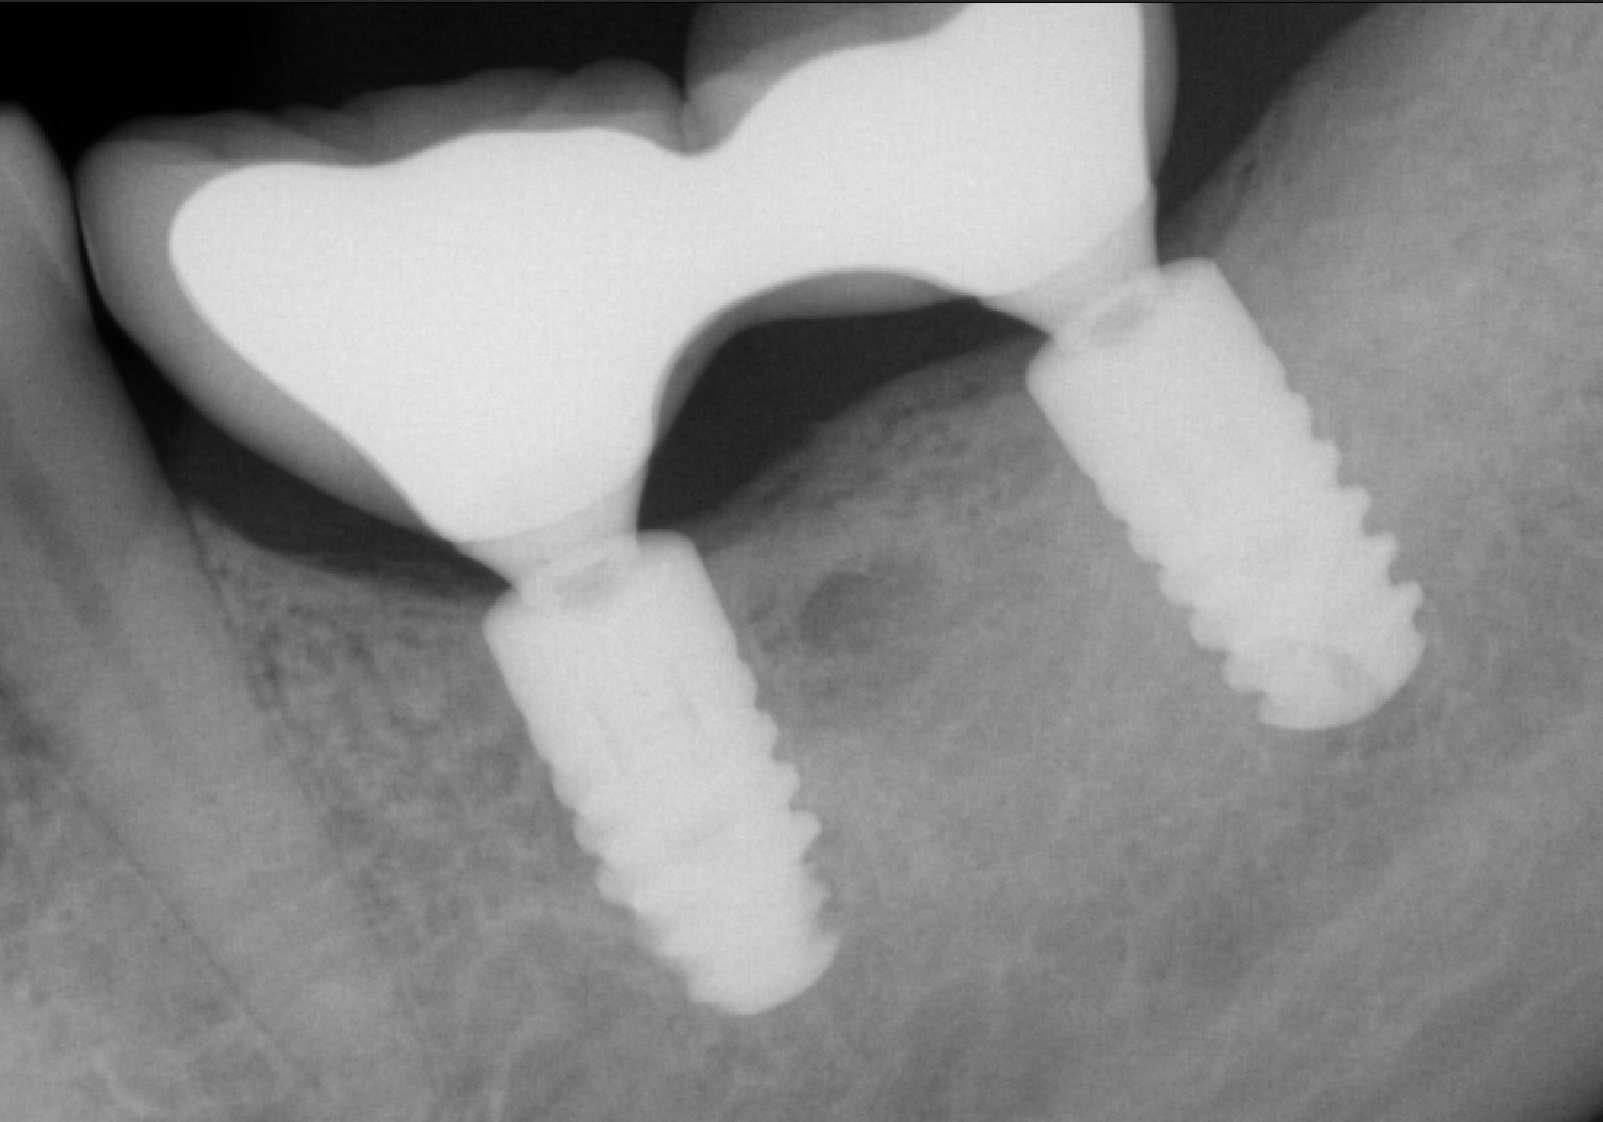

Я искренне надеялся, что это раскрутился винт, фиксирующий коронку к имплантату, но все оказалось куда прозаичнее. Так же, как и в предыдущей статье, причиной был перелом винта:

Рентгеновский снимок после извлечения винта и снятия мостовидно протеза:

Временным (!) решением данной проблемы была замена фиксирующего винта на новый и фиксация этого же мостовидного протеза на место: